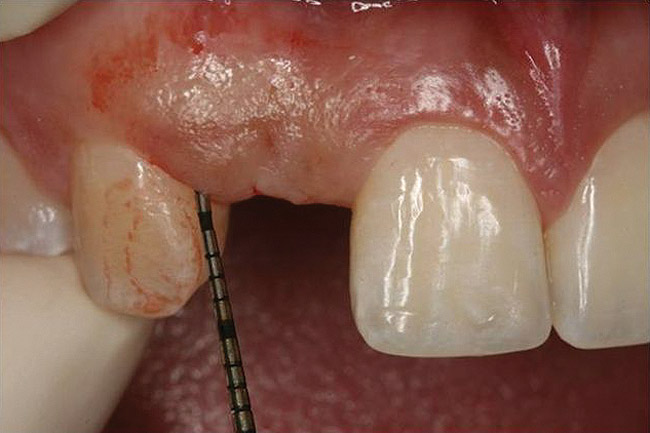

Figure 11   Clinical examination of the bound edentulous space: Measurement of the distal (Fig 10) and mesial (Fig 11) interproximal tissue height using a periodontal probe supplements data obtained from the periapical radiograph. Estimation of the buccal tissue thickness (bone sounding) is performed at the determined location of the gingival zenith using a guide developed from the diagnostic waxing (Fig 12).

Figure 11

Figure 12   Clinical examination of the bound edentulous space: Measurement of the distal (Fig 10) and mesial (Fig 11) interproximal tissue height using a periodontal probe supplements data obtained from the periapical radiograph. Estimation of the buccal tissue thickness (bone sounding) is performed at the determined location of the gingival zenith using a guide developed from the diagnostic waxing (Fig 12).

Figure 12